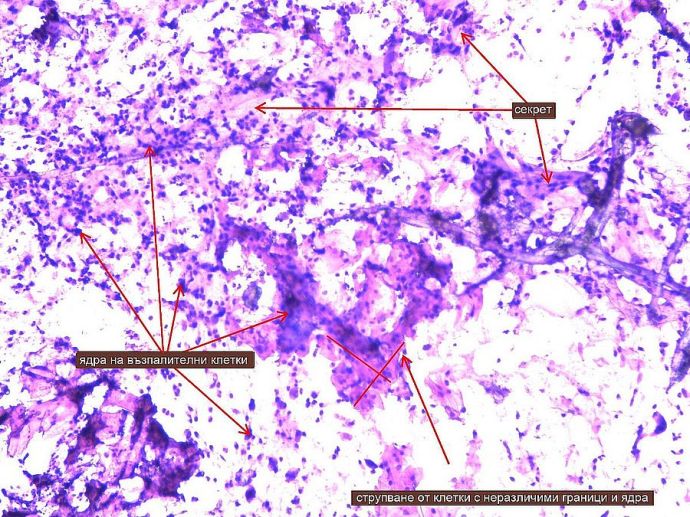

Така изглеждат под микроскоп клетките от пробата за стандартна цитонамазка

Много често стандартната цитонамазка е разстлана на няколко слоя, като клетките се наслояват една върху друга и изглеждат като стълбчета магнити, а детайлите им не могат да се отдиференцират. А ние преценяваме групата на намазката по детайлите. Затова е много важно клетките да са колкото се може по-раздалечени, да не се наслагват и да няма обекти наоколо като слуз, възпалителни клетки, еритроцити и т.н. Всичко това се постига благодарение на новия метод. ![]()

Основната разлика между двете е в качеството на взетата проба от гинеколога и видимостта на клетките и техните детайли на предметното стъкло. Именно по тях се определя има ли предракови промени. При стандартната цитонамазка гинекологът взима проба, която после се нанася на предметно стъкло, и се изпраща за изследване под микроскоп. Когато е видима на стъклото, в нея са примесени много допълнителни клетки и обекти, които замъгляват картината. Това са възпалителни клетки в различно количество в материала от шийката на матката, еритроцити – червени кръвни клетки, които се получават обикновено при самото вземане на пробата, особено ако то е по-грубо. Също така, когато посещението при гинеколога е в неправилно време от цикъла, шийката е по-ранима и изкървява, а във влагалището има много слуз. То е пълно с нея и особено в дадени периоди на цикъла замъглява клиничната картина. Това е като звездички върху екрана на телевизор, които много пречат на образа. Ако обаче се вземе течно-базирана цитология, тези проблеми на конвенционалната цитоманазка са минимизирани в голяма степен.